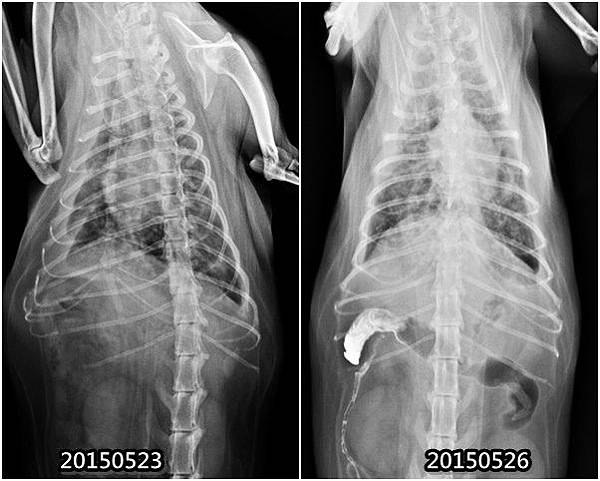

T 醫師講著灌了顯影劑,X光片已拍了兩次,發現流的很慢,可能有消化性潰瘍或常道沾黏產生

(左肺部狀況,右 腸道顯影劑)